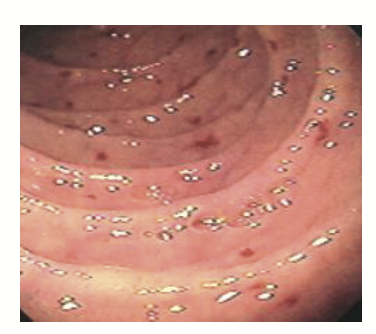

GAVE

classic antral watermelon appearance

often seen in women with autoimmune conditions

presents with IDA

Rx- APC and tranexamic acid

punctate appearance

often seen in cirrhotics

not related to portal hypertension and only resolves with liver transplant